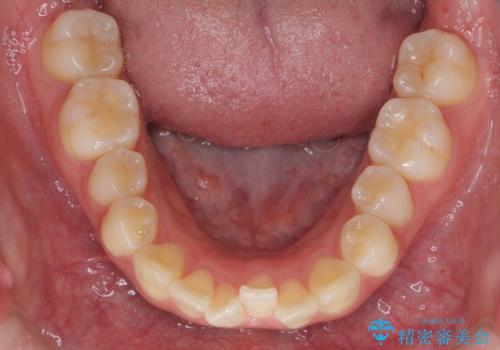

- 前歯のねじれを主訴に来院。

年齢が10代なこともあり、歯の動きは非常によく、リファインメントなしできれいに並びました。

下の前歯を少し削合して並べています。